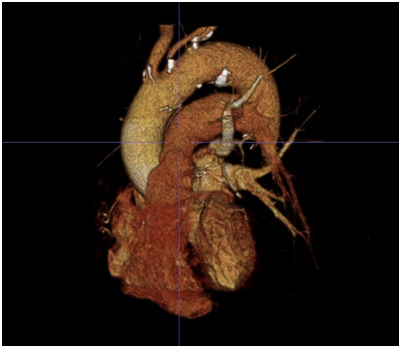

One clinical implication of the ubiquitous nature of Type III arches in our very elderly aortic stenosis patients relates to percutaneous access for interventions such as TAVR. In specific, with the left arm hyper extended over the head, the trajectory of the left axillary and left subclavian arteries falls along the trajectory of a Type III arch (Figure 3). This trajectory makes an axillary approach an attractive alternative to trans: apical and trans: aortic approaches in patients with advanced lung disease or severe peripheral artery disease (PAD) who are not good candidates for either transfemoral or transapical/transaortic approaches. Finally, this information coupled with the fact that axillary artery size is quite comparable to femoral artery size in most patients,8,9 a totally percutaneous left axillary artery approach utilizing a double Per close large bore arteriotomy closure at the end of procedure is highly feasible for a totally percutaneous TAVR as demonstrated by Shäfer et al.10 and also for totally percutaneous Impella device insertion and removal (Figures 4A to 4E) as shown by our group.8

Figure 3 3D rendering of aortic arch and origin of great vessels in the same patient.